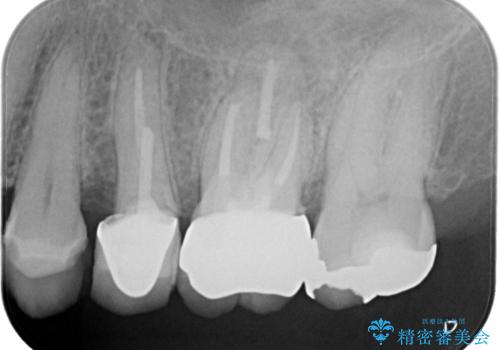

【破折ファイル除去】他院で折れた根管治療の器具をとってほしい

- 他院で折れた根管治療の器具をとってほしいという主訴で来院されました。

マイクロスコープで根管内を観察すると、除去できる状態だったため破折ファイル除去を行いオールセラミッククラウンにて修復治療しております。

通常、根尖湾曲の先にあるファイルは無理に取るより外科治療によりアプローチすることを推奨しています。